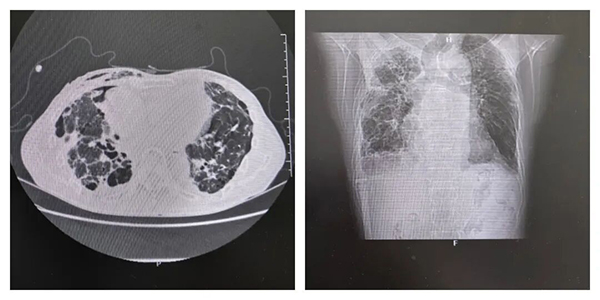

胸部CT检查显示:吴老伯右肺发生了自发性气胸,肺组织被压缩高达80%!这意味着他大部分肺部已失去通气功能,呼吸极其困难。入院后,呼吸与危重症医学科(二)主任赵焕带领团队迅速为其实施了胸腔闭式引流术,这是治疗气胸的标准手段。

(复查CT显示右肺已完全复张)

经过从活瓣植入到自体血精准封堵的阶梯式综合治疗,配合后续精心的护理与康复,吴老伯的病情终于迎来了转机,引流管中的气泡逐渐消失直至完全停止,复查CT显示,原本压缩的右肺已完全复张。近日,吴老伯各项指标恢复正常,顺利康复出院。